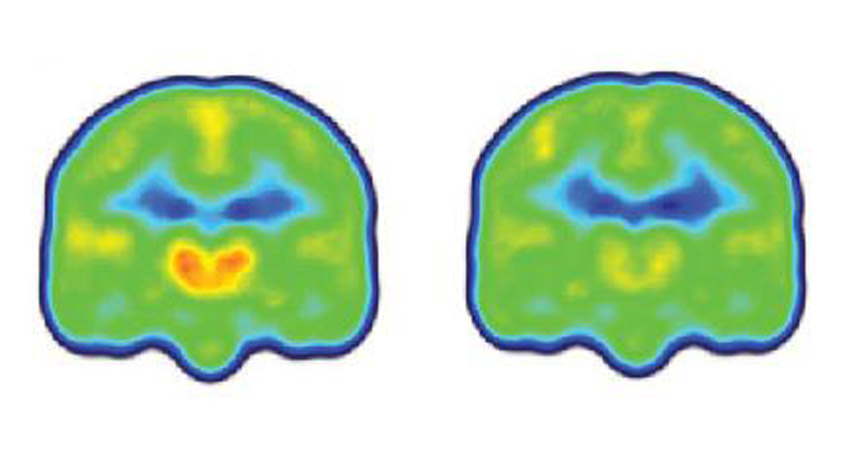

People with chronic pain (left) have higher levels of a protein linked with inflammation (orange and red) in their brains than people without chronic pain (right), suggesting that the cells that protect the brain may also cause pain.

Marco Loggia, Massachusetts General Hospital